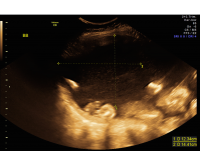

Beginning at about 16 to 18 weeks of pregnancy, all MCDA twins undergo regular ultrasound surveillance for TTTS. If excess fluid (polyhydramnios) is noted for one twin and decreased fluid (oligohydramnios) is observed for the other, then a diagnosis of TTTS is confirmed and the health of the twins is further evaluated. While a range of options exist for the management of TTTS, contemporary therapy for early-onset, advanced-stage TTTS ideally involves fetoscopic laser therapy. Pregnancies complicated by TTTS require close surveillance even after therapy, and are at high risk for premature delivery.

Twin-Twin Transfusion Syndrome